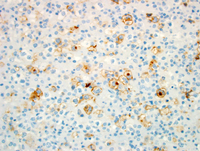

Small lymphocytic lymphoma with Richter's Syndrome, Hodgkin type.

H&E showing the small lymphocytes in the background of large atypical cells consistent with Hodgkin cells.